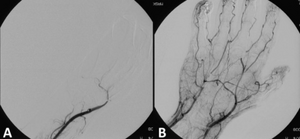

image الإنجليزية

Angiograph before and after thrombolytic therapy in a case of thrombosis on the hand.png